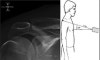

1) Lateral view(=Scapular “Y” view, Trans-scapular view)

Demonstrates: lateral projection of scapular body and humeral head overlapping the glenoid.

Helpful for: Shoulder Dislocation, Proximal Humerus Fracture, Scapula Fracture

Position: Erect with anterior aspect of affected shoulder against x-ray plate and rotating other shoulder out 40 deg°.

Beam aimed from posteriorly along scapular spine